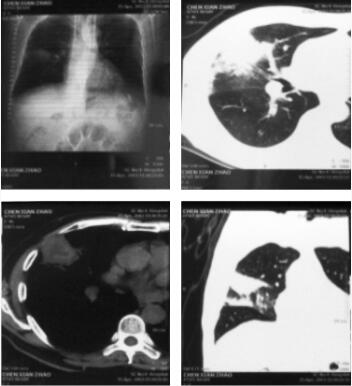

图2 患者入院后第1次胸部CT(右肺病变放大图)

住院后3天患者出现发热,体温由37.8℃升至39℃,复查降钙素原3.99ng/ml。痰涂片:入院当天:G+球菌(++),G-杆菌(+);入院第2天:G+球菌(++),G-杆菌(+),G-球菌(++);入院第3天:G+球菌(+++),G-球菌(++++),G+杆菌(+++),G-杆菌(+++)。未查见真菌,痰抗酸染色未见抗酸杆菌。第一次胸部CT(图2):右肺中叶占位性病变,病灶呈窄基底贴近胸膜,密度不均,形态不规则,明显“毛刺征”,并可见小空泡,病变周围可见斑片影及小结节影。

总结:右肺中叶占位性病变,阻塞性肺炎。更换抗生素为美罗培南1.0g q8h静滴,但患者仍出现发热,电子支气管镜:喉部、气管、隆突、左支气管、右支气管未见异常。支气管刷片、冲洗液、右肺支气管黏膜、痰液病理检查均未见肿瘤细胞,提示炎症细胞浸润,也未查见抗酸杆菌。右肺穿刺病理活检:送检组织为间质及肺泡腔内纤维组织增生,慢性炎症细胞浸润。肿瘤标记物、浅表淋巴结超声、骨ECT、痰培养及血培养未见明显异常。2天后复查胸部CT(图3):右肺中叶病变,其内见液化坏死,可见液平,周围斑片影较前明显扩大,增强扫描无强化,肺脓肿。

图3 入院后第2次胸部CT